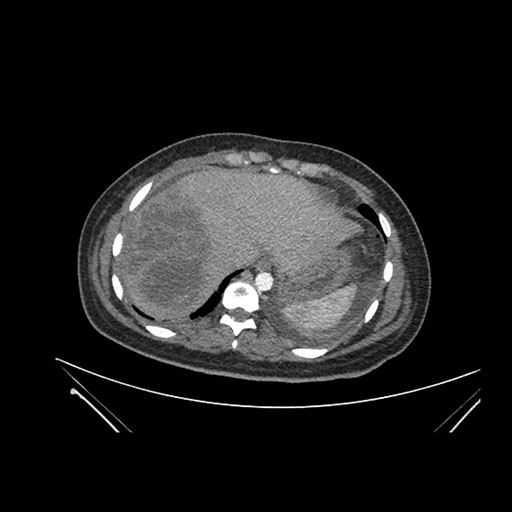

Imaging Analysis

Look through the patient's CT scan to identify any areas of concern for the necessary procedure.

Coronal Arterial